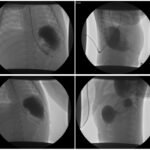

Congenital diaphragmatic hernia is usually diagnosed prenatally and surgically repaired within the first few days of life. It is very rarely associated with acute gastric volvulus, an uncommon surgical emergency in children. A male infant with atypical presentation of acute gastric volvulus was diagnosed and treated by a swift-acting team across two medical centers. The patient presented with generalized abdominal distention and non-productive retching. Upper gastrointestinal series diagnosed acute gastric volvulus. During laparoscopic intervention, the volvulized stomach and the spleen were identified within an undiagnosed congenital diaphragmatic hernia. Corrective surgery was performed, and the patient tolerated a regular diet within days and continues to do well. Given the emergent nature of acute gastric volvulus in children, a high index of suspicion is warranted to quickly initiate potentially life-saving diagnostics and treatment.